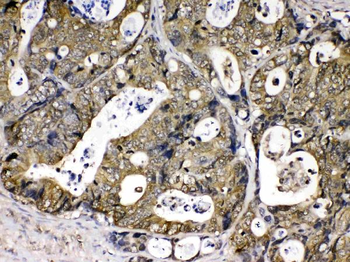

Anti-Cyclophilin A/PPIA Antibody [orb19174]

FC, ICC, IF, IHC, IHC-Fr, WB

Human, Mouse, Rat

Rabbit

Polyclonal

Unconjugated

10 μg, 100 μgCYPA Rabbit Polyclonal Antibody [orb100498]

FC, IF, IHC-Fr, IHC-P, WB

Bovine, Canine, Porcine, Rabbit

Human, Mouse, Rat

Rabbit

Polyclonal

Unconjugated